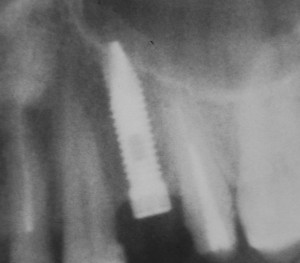

Синуслифтинг и имплантация

Конечная цель операции синуслифтинга – создание адекватных условий для установки имплантов. При этом, нередко удается провести имплантацию одновременно с операцией синуслифтинга. Как уже говорилось выше, это возможно, если существующий объем костной ткани позволяет стабилизировать имплантат заданного размера (рис 43, 44, 45):

Рисунок 43, 44, 45. Установка имплантов одномоментно с операцией синуслифтинга: слева – этап синуслифтинга, в центре – подготовка лунки под имплантат (виден спейсер и слизистая оболочка гайморовой пазухи), справа – установленный имплант

Оптимальное расстояние от дна гайморовой пазухи до верхней точки альвеолярного гребня верхней челюсти, при котором возможна стабилизация импланта длиной 10-11 мм – не менее 3-4 мм. Однако, в некоторых случаях имплантат длиной 11 мм удается стабилизировать в меньшем объеме костной ткани (рис 46, 47, 48):

Рисунок 46, 47, 48. Стабилизация импланта при толщине костной ткани менее 3 мм: слева – установка импланта после синуслифтинга, в центре – заполнение субантрального пространства спейсером, справа – рентгенологический контроль.